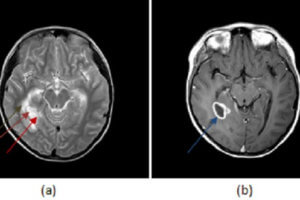

Herpes Encephalitis

Herpes simplex virus type 1 (HSV-1) is a prevalent virus with an affinity for the nervous system. Reactivation of the virus within the brain parenchyma either directly or through retrograde spread along... Read more »